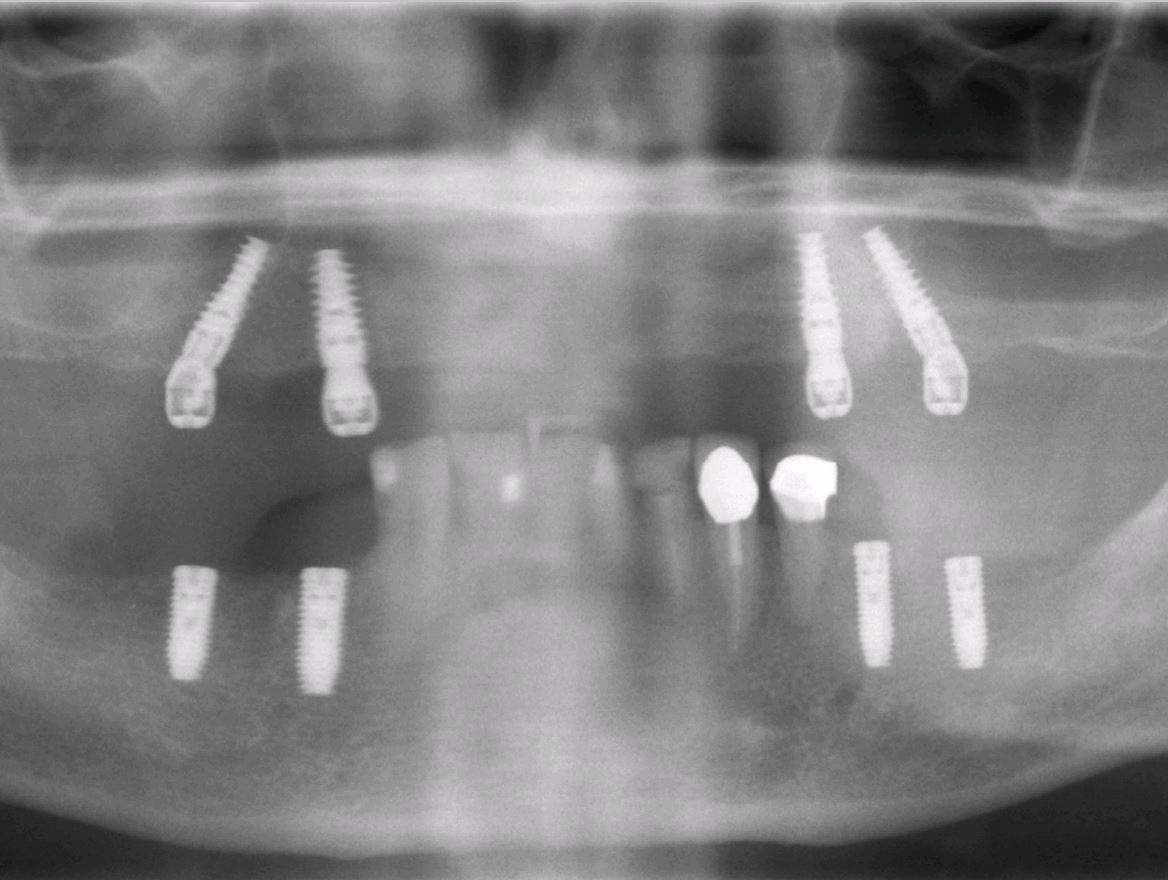

All-on-4-Behandlungskonzept

"Feste Zähne an einem Tag"

Sind nun alle Zähne des Kiefers verloren gegangen oder ist es notwendig alle restlichen Zähne zu entfernen, bleibt den Patienten normalerweise nichts anderes als eine konventionelle Vollprothese. Hier kann durch das spezielle Verfahren des Einbrigens von vier Implantaten ein Zahnersatz bereits in sehr zügiger Weise im Mund befestigt werden. Diese Methode ist an bestimmte Vorgaben gebunden und nicht immer ohne weiteres anwendbar. Bei günstigen Bedingungen kann es sogar möglich sein sogenannte "feste Zähne an einem Tag" zu bekommen.